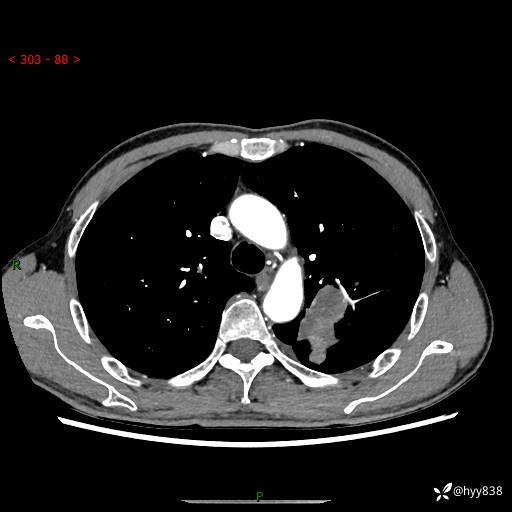

现病史:患者余4月前发现咳嗽咳痰伴痰中带血,无胸闷、胸痛、头晕、恶心、呕吐等不适,2天前因体检发现肺部结节遂于当地市第一人民医院行胸部CT薄层平扫+三维重建示:1.左肺上叶尖后段占位性病变考虑肿瘤性病变伴阻塞性肺炎,右肺上叶后段磨玻璃结节。2.肝内多发囊性灶、左肾结石。现患者为求进一步治疗,于我院门诊就诊,门诊以“肺结节”收入院。 自患病以来,精神、饮食、睡眠尚可,大小便正常,体力体重无明显减轻。

胸部CT增强扫描(外院平扫)